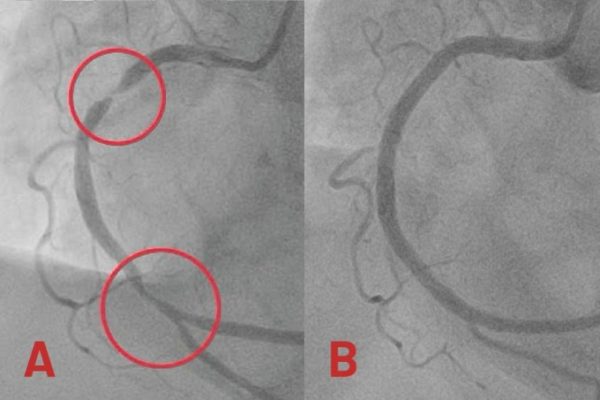

Bà Keelin, một bệnh nhân nhập viện tại Bệnh viện Đa khoa Tâm Anh TP HCM, đã trải qua một tình huống nguy kịch do nhầm lẫn các triệu chứng của nhồi máu cơ tim. Ban đầu, bà chỉ cảm thấy đau vùng thượng vị, mệt mỏi và khó thở, khiến bà nghĩ rằng mình…